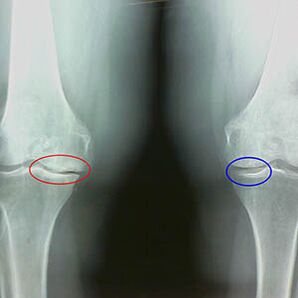

Ceļa artrozes otrā posma agrīnās X -ray iezīmes:

- stilba kaula stilba kaula stilba kaula smailās malas, kur ir piestiprināta krusta formas saišu;

- locītavas spraugas sašaurināšanās mediālajā pusē;

- Kaulu condyles smailās malas mediālajās pusēs, retāk sānos - atkarībā no valgusa attīstības vai varioru locītavas deformācijas.

Uz otro posmu Larsenā Ir raksturīga kopējās spraugas sašaurināšanās par vairāk nekā 50%, bet to var pārbaudīt tikai dinamikā vai salīdzinājumā ar atšķirīgu locītavu.